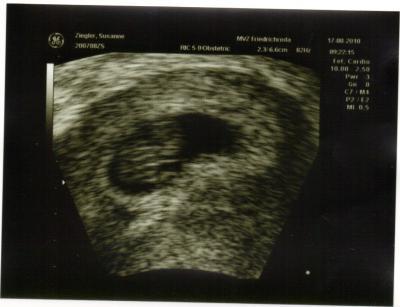

und hier noch ein pic vom bauchzwerg!

Dein Baby hat sich da ja schön eingekuschelt....

Klasse,dann kannst du die nächsten Wochen beruhigt sein.Dein Mäuschen hat sich auch so eingerollt wie unseres im letzten US.:) LG,Anja